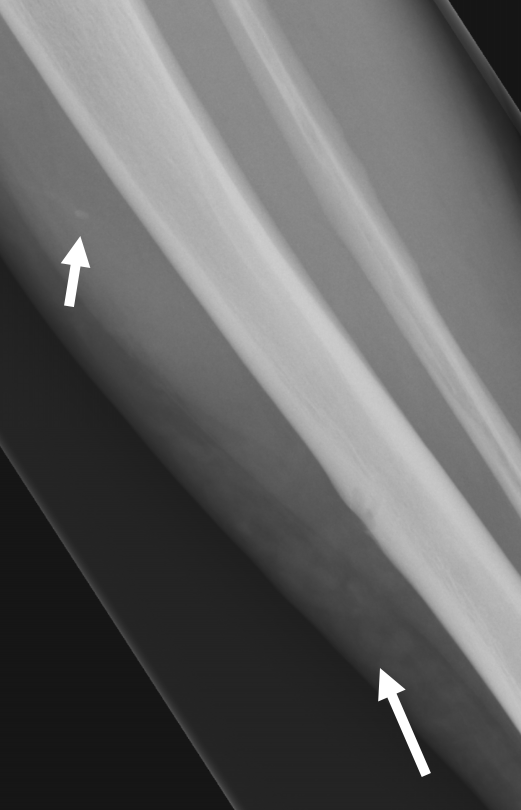

- Erosion oder kleine Zyste im MC-5 Köpfchen (kurzer Pfeil) und Knochenmarködem im Os hamatum (langer Pfeil) T1 FS KM

- Diffuses Weichteilödem entlang des 5. Strahles mit korrespondierender KM- Aufnahme (Pfeile) (T1 FS KM)

- Zusätzliche diffuse ödematöse Veränderungen im Subkutangewebe der gesamten Hand (Pfeile) mit fehlender oder nur sehr wenig korrespondierender KM Aufnahme